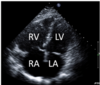

21.2 A 69-year-old woman has a recent onset of dyspnoea and undergoes a right heart

catheterisation, with results displayed below. Her pulmonary capillary wedge pressure is 10

mmHg. The most likely diagnosis is

A

Assuming pathology is pre-lung (normal PCWP).

? Pulmonary stenosis